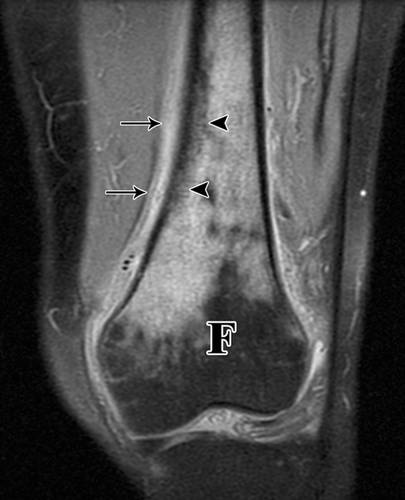

10A - 58岁男性转移性腺癌MRI冠状位。

![]()

10B - 58岁男性转移性腺癌CT引导下穿刺。